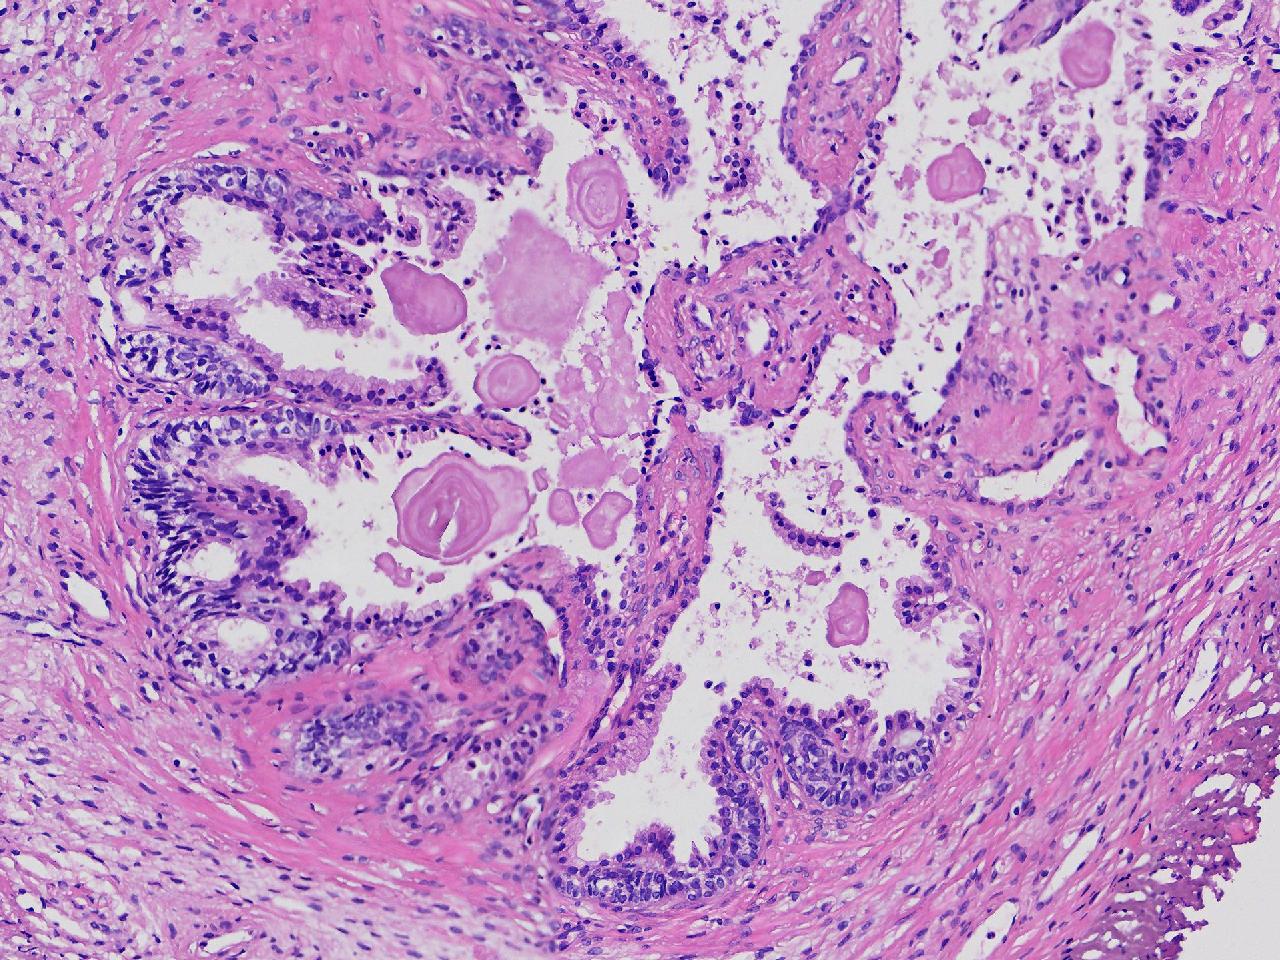

这些腺体有问题吗?

性别

男

年龄

77岁

男,77岁,排尿困难2年,尿潴留3天。

标本名称

电切前列腺组织

大体所见

条索状软组织多块,5X5X4厘米。

图1